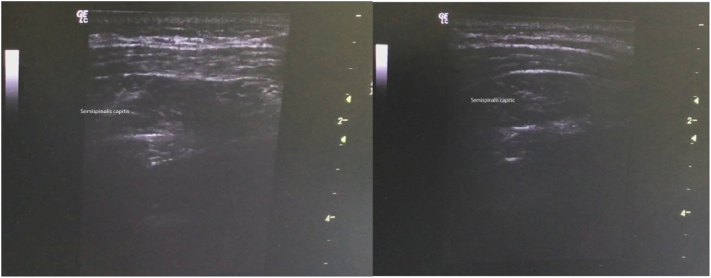

This 67-year-old female patient presented with a 5-year-old goose-neck posture abnormality. Initially, the patient complained of tension in the back of the neck and irregular extension movement of the head. Physical examination found a dystonic movement with a backward extension of the head and a forward sagittal shift of the neck that caused the chin to be pushed forward (Fig. 1). Brain and neck MRI were normal. After informed consent, her neck was investigated using ultrasound and EMG. The semispinalis capitis muscles were hypertrophic and overactive bilaterally (Fig. 2) and the trapezius muscles also showed increased activity bilaterally. We did not find increased activity of the splenius capitis, levator scapula, or sternocleidomastoid muscles bilaterally. Seventy five units of abobotulinum toxin were injected into each of the lateral and medial aspects of each semispinalis capitis; 50 units of abobotulinum toxin were injected into each upper part of the trapezius. On examination 2 weeks postinjection, the patient had improved significantly in both head extension and forward sagittal shift, with minor neck pain (Fig. 1).

Fig. 2.

Hypertrophic semispinalis capitis muscles.